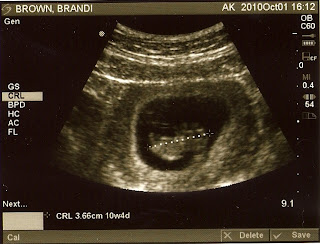

I am officially 11 weeks pregnant today! We found out August 25th that we were expecting, and while I was the one to freak out, Danny was the one who was more excited and happy at the beginning. That is not how I would have expected it to go. Last Friday we got to see Baby Brown for the first time, which was a more moving and joyful experience than I can really explain. I have been so worried this entire pregnancy that something was going to go wrong, so just being able to see and hear a heart beat, and see the tiny baby growing in me helped relieve many of my fears and anxiety. I'm really trying to hand it all over to God right now, knowing that at this point there isn't much I can do to control how this pregnancy goes. In preparation for raising this baby, Danny and I are currently trying to get our lives more focused on God, living with a love for the Gospel ourselves so that our child will see that in us, and hopefully desire to have that as well! We are lucky to be surrounded by some amazing and Godly parents as well as excellent teaching and support for anyone who is raising a family in this church!

The first one is where they measured him. He's 3 1/2 centimeters long!